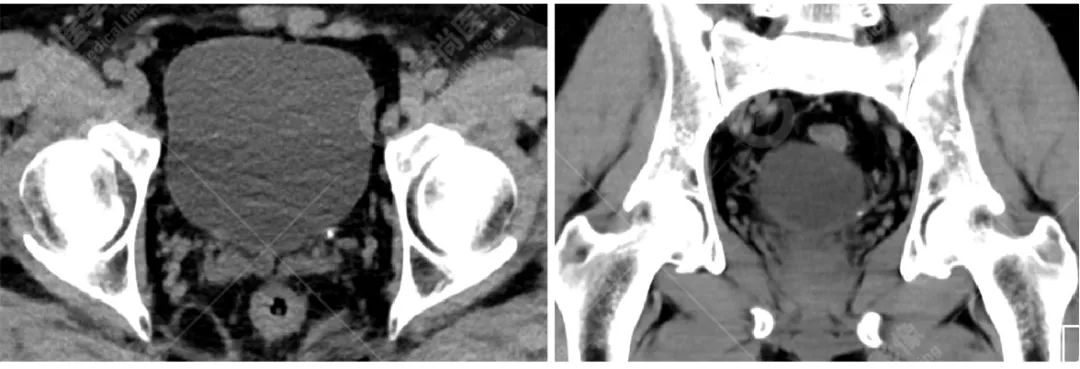

病例三

病史摘要:

患者左输尿管膀胱入口处小结石,双能量 CT 结石分析示其主要成分为尿酸。

CT 平扫因其安全性和高度敏感性已成为评估泌尿系结石的标准检查方法。而双源 CT(dual-source computed tomography,DSCT)在一次扫描过程中能够同时进行低能量和高能量扫描,使其拥有能够对电子密度相同但光子吸收能力不同的结石进行鉴别的能力。

计算感兴趣区结石在低能量和高能量原位扫描下的衰减值比值(AR 值),与体外结石的已知化学成分的 AR 值进行对比,因此得到体内结石的化学成分。(此步骤在工作站进行,如上成分标识图)